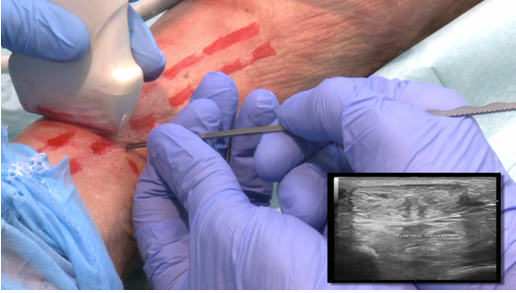

Imagen intraoperatoria de tratamiento tenotomía del delgado plantar con cirugía ecoguida en paciente real. Visión ecográfico en paraleleo

Se localizan el delgado plantar, el Aquiles, el surco de fricción y los vasos tibiales posteriores.

Bajo ecografía, se realiza la sección completa sin afectar al Aquiles ni al paratendón.

El cirujano comprueba en tiempo real que no existe tensión residual ni conflicto mecánico.